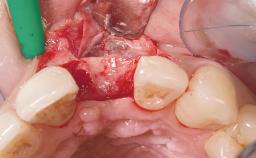

Immediate Flapless Placement of an Implant in a Maxillary Right Lateral Incisor Site

This 43-year-old male patient, a non-smoker, came to our practice because of a fracture of tooth 12 caused by a bicycle accident. Due to the combined para- and infrabony crown and root fracture, tooth extraction, and subsequent implant placement were suggested to the patient as the therapy of choice. The patient had high esthetic expectations with regard to the treatment outcome and asked for an immediate fixed provisional restoration. His individual esthetic risk profile summed up to a medium esthetic risk.

| Loading Protocol | Immediate |

| Provisional Implant-Supported Prosthesis | Prosthodontic margin > 3 mm apical to mucosal margin Prosthodontic margin > 3 mm apical to mucosal margin |